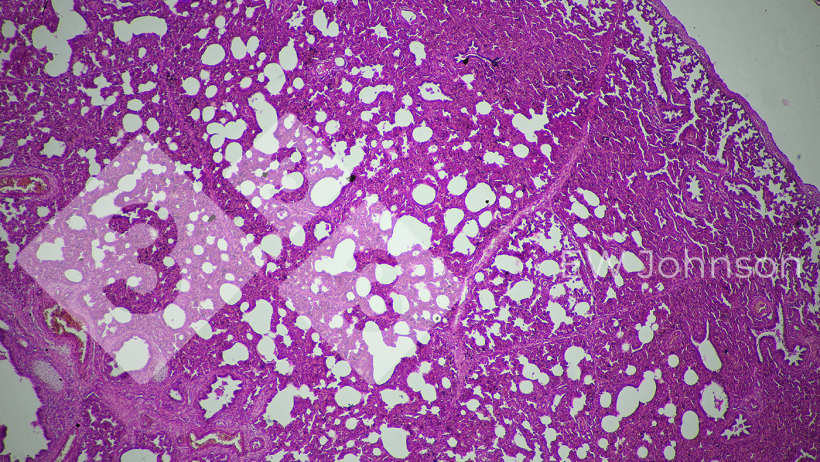

Wynik badania PCR był ujemny dla PRRS, rzekomego pomoru świń (PRV, choroba Aujeszky'ego), cirkowirusa świń PCV2 i PCV3, klasycznego pomoru świń (CSF) i afrykańskiego pomoru świń (ASF). Stado było wolne od PRRS, PRV, CSF i ASF przed tym zdarzeniem. PCR dla Getahvirusa w płucach prosiąt był silnie dodatni. Badanie histopatologiczne wykazało ciężkie śródmiąższowe zapalenie płuc (ryc. 3) i włóknisto-krwotoczne zapalenie opon mózgowych (ryc. 4). Postawiono diagnozę okołoporodowej choroby getahvirusowej. Gospodarstwo zostało poinformowane, że choroba ta jest przenoszona głównie przez komary i wprowadzono środki kontroli. W gospodarstwie nie wystąpiły dalsze przypadki ani objawy kliniczne, a produkcja powróciła do normalnego poziomu.

Ryc. 3. Śródmiąższowe zapalenie płuc sugeruje możliwą przyczynę wirusową